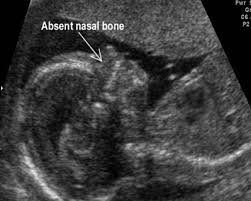

2.) Downs Syndrome

Downs Syndrome is a genetic condition that causes developmental and physical delays.

Due to Downs being linked to genetics, it is not diagnosable through ultrasound alone. The only 100% way to determine if the baby is affected while in utero is by an amniocentesis (inserting a needle through the belly, extracting a sample of amniotic fluid, and testing the baby’s genetic material in the fluid).

However, there are soft markers (physical indicatations of a baby possibly being affected) for Downs that can be detected with ultrasound. These include a short/absent nasal bone, a protruding tongue, fluid in the kidneys, etc. These soft markers, if seen, can be relayed to the patient and may give cause for testing, if the patient desires it.